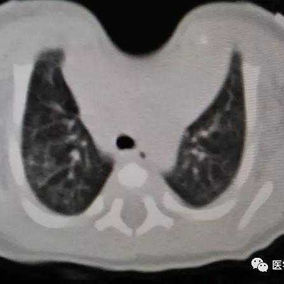

The patient was a one-month-old infant who was discovered to have an abnormality in the anterior chest wall shortly after birth. Specifically, there was a pronounced depression in the midline of the upper chest wall where the protection of bone structures was noticeably absent. The infant was diagnosed with sternal cleft and congenital heart disease. Due to the infant's poor health, surgical intervention has been postponed temporarily. Over time, the infant's condition gradually worsened, resulting in breathing difficulties and triggering a lung infection.

Preoperative Examination

There is a noticeable depression in the center of the chest wall, accompanied by obvious paradoxical respiration. This area shows large-scale deficiency or absence of bone structures, with only about 1 cm of bone structure remaining at the inferior end of the sternum, connecting both sides of the chest wall. Additionally, the patient suffers from congenital heart diseases, including ventricular septal defect and patent foramen ovale, which have led to abnormal heart rhythms and sinus tachycardia.